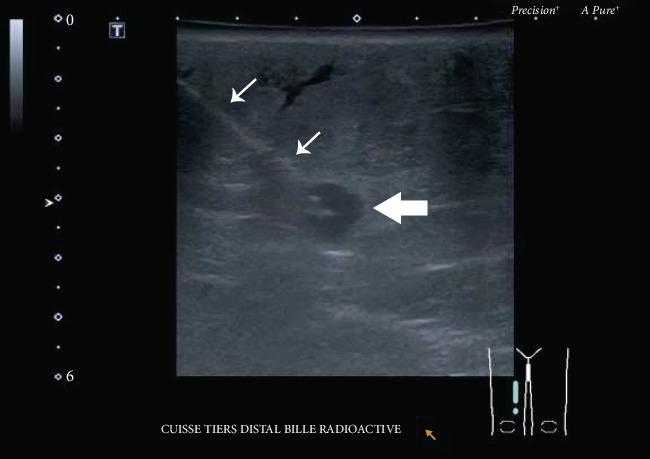

默克尔细胞癌是一种进展迅速的非黑色素瘤皮肤癌,复发风险高。当复发发生时,其预后较差,且缺乏针对此类病例的管理指南。本文描述了一个具有挑战性的病例,其中创新性地使用碘 - 125放射性粒子使我们能够精确识别并切除两个不可触及的复发性结节。由于过去两次切除和两个疗程的放疗后存在瘢痕组织,手术的安全性和准确性受到了影响。放射性粒子定位在乳腺癌中是一种广为人知的操作,显示出在其他癌症类型和复杂临床情况中扩展应用的潜力。

https://cdn.ncbi.nlm.nih.gov/pmc/blobs/9d98/7321529/80d6ca0b1076/CRIS2020-1789185.003.jpg

https://cdn.ncbi.nlm.nih.gov/pmc/blobs/9d98/7321529/930949cba570/CRIS2020-1789185.001.jpg

https://cdn.ncbi.nlm.nih.gov/pmc/blobs/9d98/7321529/e339b5685cc1/CRIS2020-1789185.002.jpg